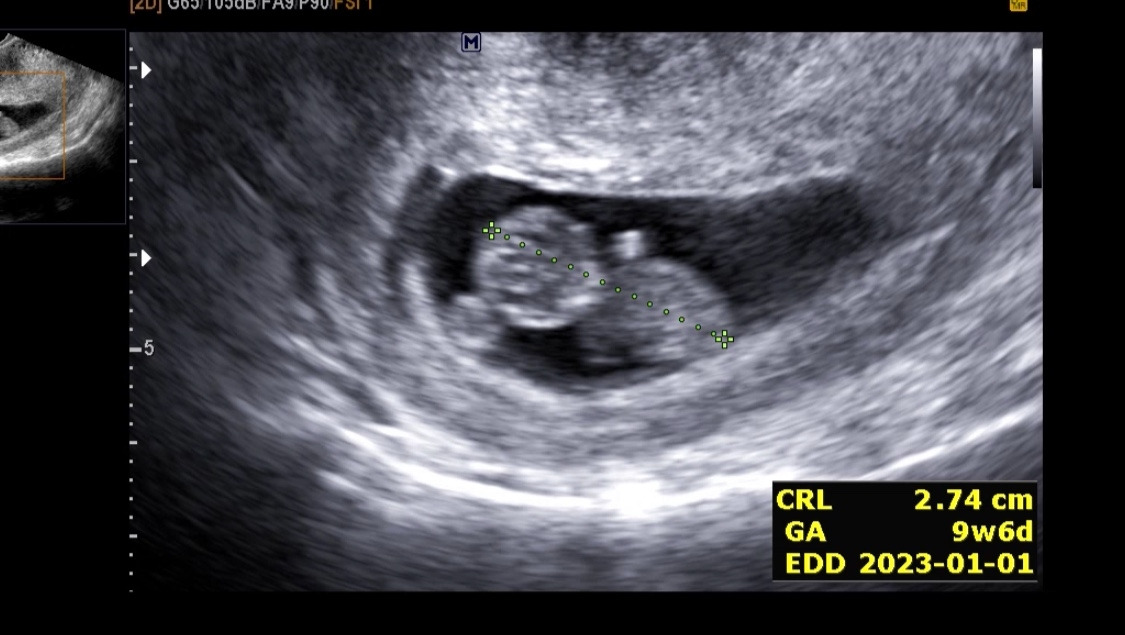

병원 진료 예약일이다. 오늘은 어떤 아기의 모습을 볼 수 있을까 두근거리는 마음으로 집을 나섰다. 예진실에서 체중과 혈압을 재고, 다음 진료 때 있을 기형아 검사 관련 설명을 간단하게 들었다. 진료실로 들어가서 오늘도 역시 질초음파로 아기가 잘 있는지 확인했다. 한눈에 봐도 아기임을 알 수 있을 정도로 아기가 많이 컸다. 오늘재는 아기의 머리-엉덩이 길이로 분만예정일을 확정한다. 이후에는 분만예정일이 바뀌지 않으며, 주수보다 아기가 작다, 크다를 판단한다. 이렇게 잰 아기의 머리-엉덩이 길이는 2.74cm, 주수는 9주 6일로 하루 앞당겨졌으며 분만예정일은 2023년 1월 1일로 정해졌다.

초음파로 만난 아기의 모습이 너무 귀여웠다. 3cm도 안 되는 작고 소중한 아기가 꼬물꼬물 움직였다. 진심으로 아기를 좋아하시는 것 같은 주치의 선생님도 너무 귀엽다며 웃으셨다. 벌써부터 도치맘이 되는 것인가...

의사 선생님의 상담내용을 기록하자면,

아기의 크기, 움직임, 심박수, 양수의 양 모두 정상이다.

이전에 보이던 피고임은 없어졌다. 유산의 위험은 매우 낮아졌다고 할 수 있다.